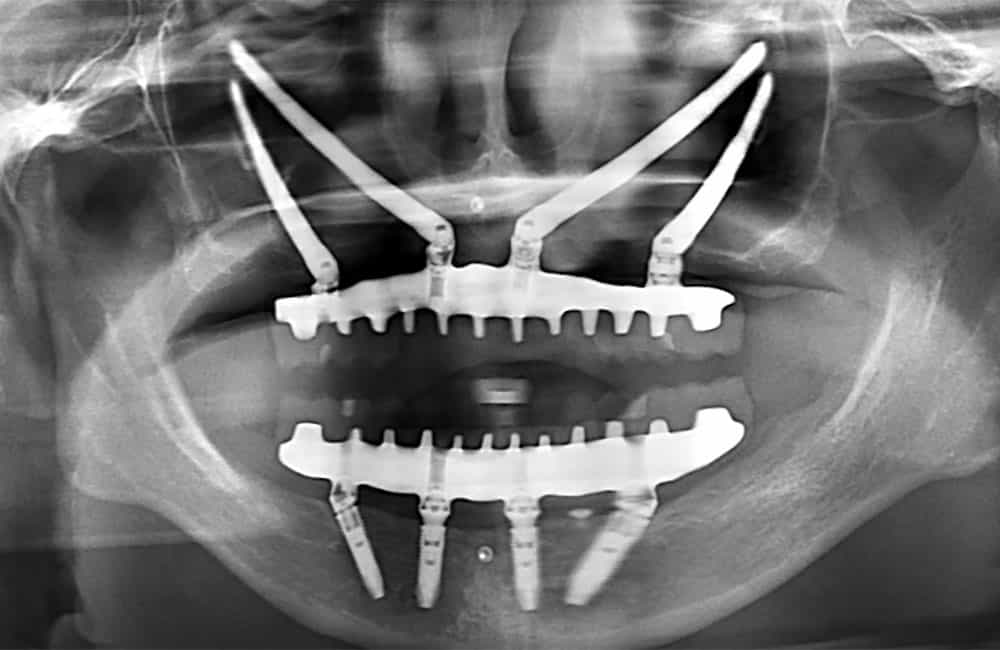

他院でザイゴマインプラント治療を受けた後、仮歯の噛み合わせが悪いため噛みづらく顔貌も変わってしまった。また頬に違和感を感じたため当院を受診。

術前のパノラマX線画像

左右のザイゴマインプラントが頬骨から大きく飛び出し頬を触ると違和感がある -

術後のパノラマX線画像

前方のインプラントは残し、他院埋入のザイゴマインプラントを除去し、同時に新しいザイゴマインプラントを適切な位置に再埋入を行っております。治療後数年経過しておりますが良好な状態を保っております。